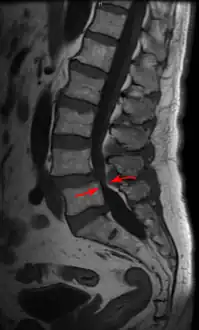

| Lumbar vertebra showing central stenosis and lateral recess stenosis. | |

Spinal stenosis may be congenital (rarely) or acquired (degenerative), overlapping changes normally seen in the aging spine.[7][8] Stenosis can occur as either central stenosis (the narrowing of the entire canal) or foraminal stenosis (the narrowing of the foramen through which the nerve root exits the spinal canal). Severe narrowing of the lateral portion of the canal is called lateral recess stenosis. The ligamentum flavum (yellow ligament), an important structural component intimately adjacent to the posterior portion of the dural sac (nerve sac) can become thickened and cause stenosis. The articular facets, also in the posterior portion of the bony spine can become thickened and enlarged, causing stenosis. These changes are often called "trophic changes" or "facet trophism" in radiology reports. As the canal becomes smaller, resembling a triangular shape, it is called a "trefoil" canal.